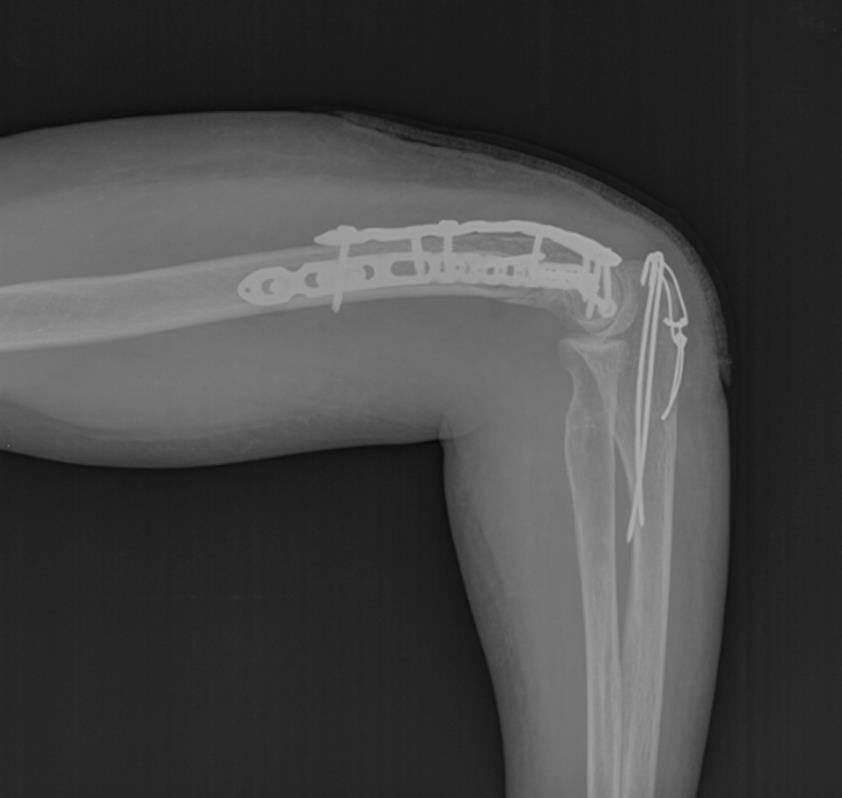

Ещё один клинический пример остеосинтеза тяжёлого перелома мыщелков плеча с использованием пластин с угловой стабильностью Synthes.

Пациентка Х, 54 лет, получила внутрисуставной Y-образный перелом мыщелков плеча. Смещение костных отломков настолько значительно, что диафиз плечевой кости близок к тому чтобы перфорировать кожу.

В случае настолько грубого смещения при первичном осмотре целесообразно выполнить анестезию перелома и устранить смещение с фиксацией конечности в задней гипсовой лонгтеной повязке. После обследования и предоперационной подготовки пациентка взята в операционную. Выполнен остеосинтез при помощи пластин с угловой стабильностью Synthes.

Послеоперационные рентгенограммы показывают, что смещение отломков полностью устранено, нормальные взаимоотношения костей верхней конечности восстановлены.

В ходе операции необходимо оценивать стабильность остеосинтеза к движениям в суставе, так как послеоперационный протокол предполагает раннюю нагрузку уже через 1-2 дня после операции. Ранние движения в суставе препятствуют образованию грубых рубцов и спаек, которые в противном случае могут вызвать стойкое ограничение движений в суставе.